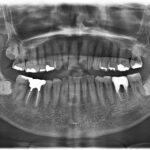

「アメリカ式根管治療」当院がこだわる”治す”ための治療スタンダード

みなさんお元気ですか?たまに歯の根っこあたりが腫れていた医院に痛い患者さんが来院 ...